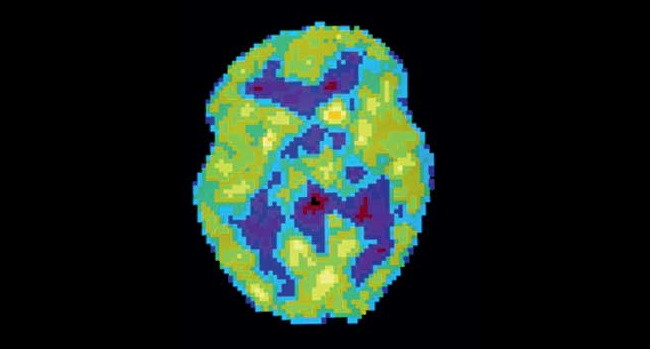

Активность мозга сильно различается не только во время бодрствования и сна — есть множество промежуточных состояний, которые можно различить во время позитронно-эмиссионной томографии.